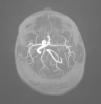

Presentamos el caso de un varón de 3 meses de edad, con una lesión vascular en la zona de la rama mandibular del nervio trigémino izquierdo (V3 izquierda), de aparición a los 15 días de vida con posterior crecimiento (fig. 1). Realizamos el diagnóstico de hemangioma facial lineal, por lo que había que descartar una asociación PHACES, acrónimo de malformaciones de la fosa posterior (P), hemangioma segmentario cervicofacial (H), malformaciones arteriales cervicocraneales (A), defectos cardíacos o de los grandes vasos (C), anomalías oculares (E) y defectos esternales o de la línea media supraumbilical (S)1. Solicitamos una angioresonancia en la que se observaban una serie de alteraciones: hipoplasia de arco aórtico con anomalía en la salida de troncos supraaórticos, hipoplasia/aplasia de arteria carótida interna izquierda y alteraciones en el polígono de Willis (figs. 2 y 3). Con todos estos datos confirmamos el diagnóstico de PHACES. Actualmente, el paciente se encuentra en seguimiento por los servicios de dermatología, neurología, oftalmología y cardiología, y no ha presentado complicaciones.